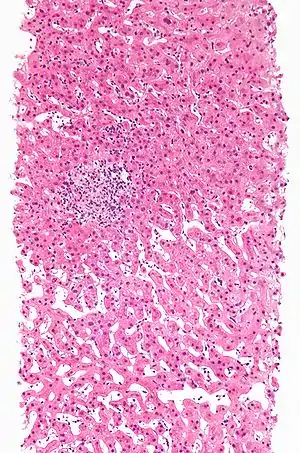

Hepatotoxicitate

Hepatotoxicitatea implică o afectare la nivel hepatic și poate să fie indusă prin tratament medicamentos.[2] Medicamentele hepatotoxice pot provoca o insuficiență hepatică acută.[3] Mai mult de 900 de medicamente au fost incriminate în cauzarea lezărilor hepatice,[4] exemple fiind: carbamazepina, paracetamolul, etopozidul, nefazodona și metotrexatul.[5]